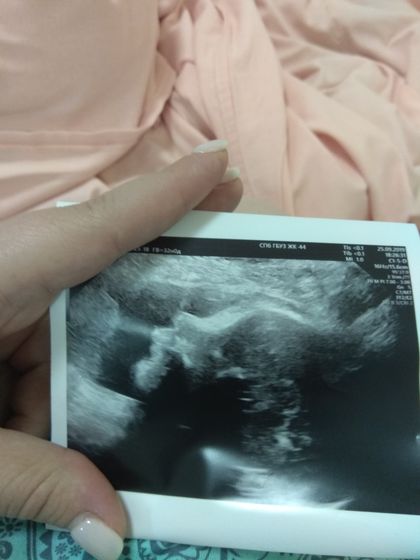

Короткая шейка. Ну вот я вчера и сходила к гине в ЖК. Пожаловалась на тянущие боли и повезло мне в одном: был талончик на скрининг сразу через 30 минут. Посмотрели малыша: все в порядке, опережает на недельку, вес 2045гр.а потом посмотрели шейку матки: 05.09 она была 40мм, а вчера стала 22,3 мм. С такими показаниям и госпитализировали в род дом. Ничего плохого не могу сказать, даже наоборот, здесь очень отзывчивый персонал(род дом 38 им. Семашко), бережное отношение. Прокапали магнезию, уже ничего болит. Прилагаю фоточку моего малыша